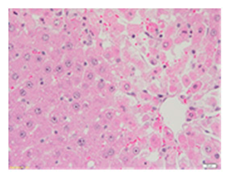

Liver wet weights of all rat groups showed no significant differences (Table 8). According to histochemical hematoxylin and eosin (H&E) staining, treatment with the highest dose of MPE (1000 mg/kg BW) did not result in morphological changes in the liver tissue (B) when compared with DI water treatment (A). Obviously, CCl4 induction (ip)/DI water treatment (po) caused hepatoxicity, which was indicated by a severe degree of fatty changes and fatty cysts in the liver tissue (C), whereas pretreatments of silymarin (100 mg/kg BW, po) effectively decreased the degree of fatty changes and fatty cysts in the liver when compared with the CCl4/DI water group. Indeed, MPE (250 and 1000 mg/kg BW, po) lowered the degree of lipid accumulation in the liver; inversely, MPE (500 mg/kg BW, po) exhibited a severe degree of lipid accumulation. Apparently, taking paracetamol (2 g/kg BW) induced a severe degree of hepatic necrosis when compared with rats that had not received the treatment. Similarly, pretreatments of silymarin (100 mg/kg BW, po) and MPE (250 and 1000 mg/kg BW, po) revealed a mild degree of hepatic necrosis, while MPE (500 mg/kg BW, po) revealed a moderate to severe degree of hepatic necrosis. Accordingly, the findings imply that the consumption of MPE (1000 mg/kg BW) was not harmful to the liver of healthy rats, while MPE (250 mg/kg BW) did improve fat deposition in the livers of CCl4-fed rats and offered protection against liver cell damage in paracetamol-fed rats.

Wet weight values (mean ± SD) and H&E staining of liver from rats with hepatotoxicity induced by CCl4 and paracetamol.

Each liver was embedded in a paraffin block, cut into slides, deparaffinized, and stained with hematoxylin and eosin (H&E) dye. The liver tissue sections were examined in terms of their histopathological status and photographed under light microscopy by a qualified expert clinical pathologist at the Department of Pathology, Faculty of Medicine, Chiang Mai University, Thailand.